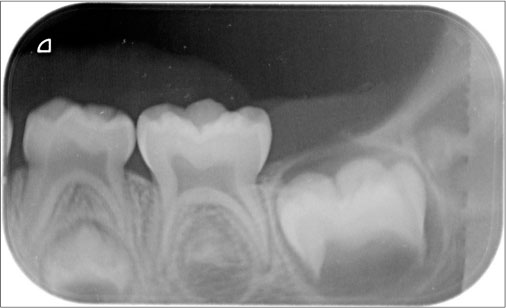

A 4-year-old female patient came with a complaint of growth in the lower back tooth region of lower jaw for 1 week. Parents of the patient noticed the growth a week back which was smaller in size initially which increased suddenly to the present size. Growth was not associated with pain or any other symptoms initially but later developed discomfort while eating associated with mild pain. The patient was given anti-inflammatory medication for the relief of pain and swelling for about 3 days, but there was no reduction in size of the growth. Medical and family histories were noncontributory. On extraoral examination, fullness is seen on the left lower third of face. A solitary left submandibular lymph node enlargement is felt, which is freely movable and tender. Intraorally, an exophytic growth was seen arising from gingiva in relation to 73, 74, and 75 tooth region [Figure 1] measured approximately around size 2 cm × 3 cm, slight pale in color with pinpoint erythematous areas. This appeared to be covered by keratotic surface and seemed to have papillary projections. On palpation, the lesion was pedunculated fibrous inconsistency, nontender, and slight bleeding on provocation, and diascopy test was negative. Considering the patient’s history and clinical examination, a provisional differential diagnosis was arrived which is as follows PG, verrucous hyperplasia, hemangioma, peripheral giant-cell granuloma, peripheral ossifying fibroma, fibroma, and peripheral odontogenic fibroma. The following sets of radiographs were advised to rule out any bony involvement. Intraoral periapical radiograph (IOPA) and occlusal radiographs showed soft-tissue shadow with respect to 73, 74, and 75 [Figure 2] and [3]. Later, complete blood picture was done which did not show any variations from the normal limits. The lesion was subjected for excisional biopsy under local anesthesia [Figure 4] and [5] and subjected to histopathological examination which revealed to be angiomatous granuloma [Figure 6] and [7]. The patient was followed up for 1 year after surgery and there was no evidence of recurrence.

| Figure. 2 Intraoral periapical radiograph showing soft-tissue shadow in relation to 74 and 75